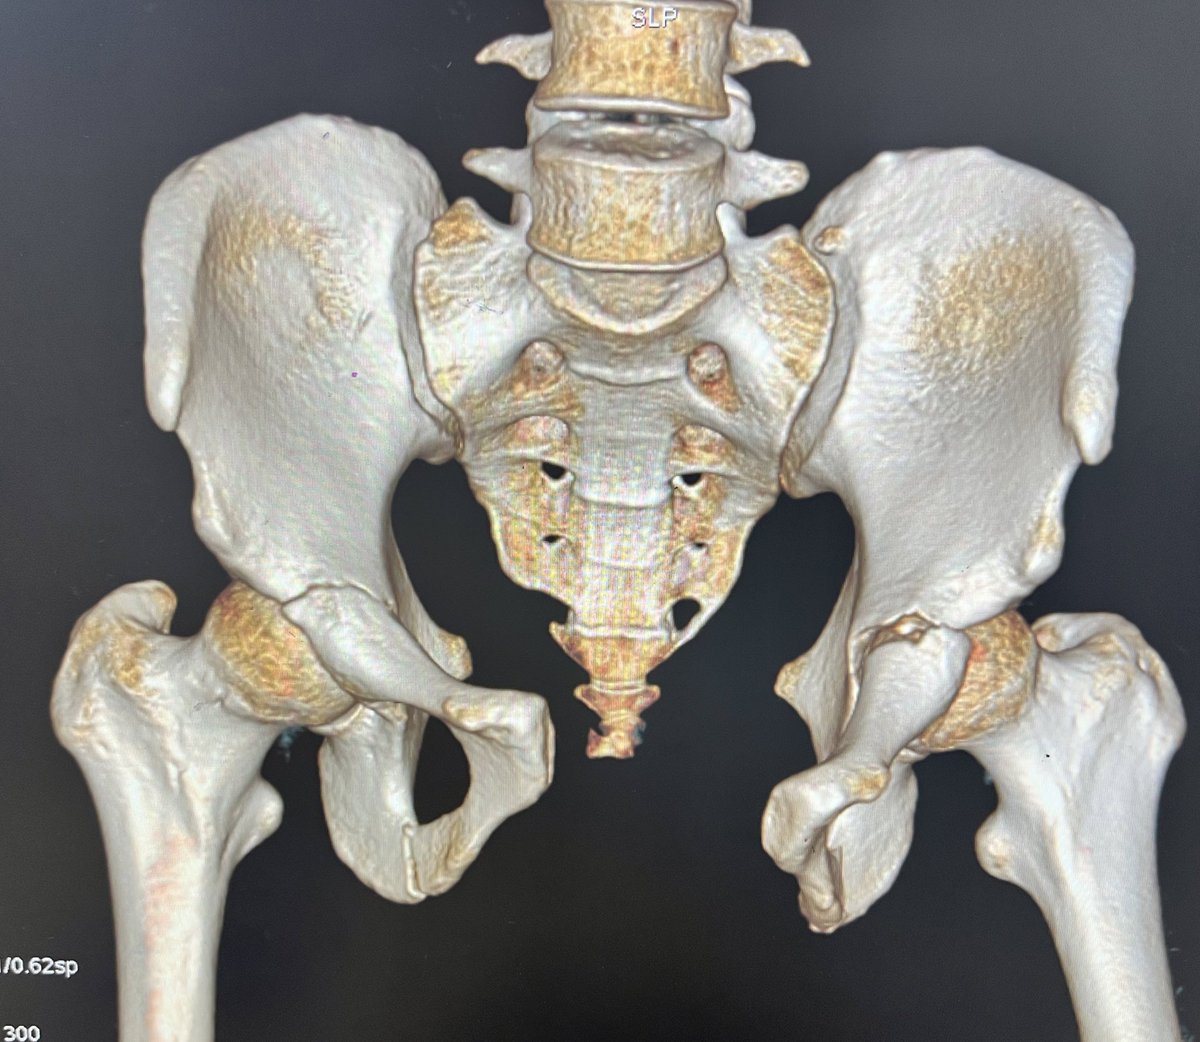

24 m, RTA, has SIJ, diastasis and bilateral pubic rami fractures. After fixing SI Joints, how would you manage the antr ring injury?

Pfannensteil and plate the symphysis? AIP and go supr to both fractures?

Infix?

Would like to hear your thoughts #orthotwitter

@centerofhip @JaiRawal12 I’d plate the symphysis and put screws in the rami/AC bilaterally. Assuming there is no bladder injury.